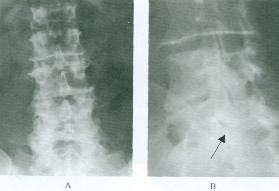

1.X線表現 骨關節的X線改變要在發病後2周方才顯示出來,有時要1個月後才出現,在6個月以內屬急性期改變;6個月以後為慢性期改變。急性期改變主要是受累關節周圍軟組織腫脹,骨質疏鬆,骨質破壞和關節損害。慢性期改變主要是骨質增生、硬化和關節強直,局部軟組織腫脹表現為關節周圍軟組織密度增高、層次不清,皮下脂肪透明度減低;重者有網織狀陰影,關節囊腫大,密度增高,輪廓多較清晰。這種改變是早期的主要所見,但不具特異性。慢性期軟組織陰影縮小,且長期難以消失。少數病例在受累骨質鄰近的軟組織中出現小片狀或團塊狀鈣化或骨化陰影,骨關節方面的改變在早期是骨質疏鬆和骨小梁模糊或中斷,局限於近關節的骨端,與類風濕關節炎的早期骨質疏鬆相似 急性骨質破壞往往在骨端的一側或雙側有一個或多個小圓形蟲蝕狀破壞,邊界清晰,常見於肌腱附著的骨隆突區。與此同時,附近可有單層細條狀或不規則骨膜增生。本病後期的骨關節改變主要是在原來破壞區周圍有骨質增生、硬化,破壞區邊界清晰,緻密,形成硬化緻密的小環形灶,手、足管狀骨常有整個骨幹增粗,但無死骨。在骨骺未融合者,破壞區可在骨骺或乾骺端,易引起骨骺早期閉合。

關節間隙的改變表現為早期的關節間隙不對稱狹窄、模糊,關節軟骨面不平整,關節變形,甚至有半脫位,軟骨下常有骨質破壞。在本病後期,可發現關節有自行融合趨勢,可形成關節強直,但融合多不完全。